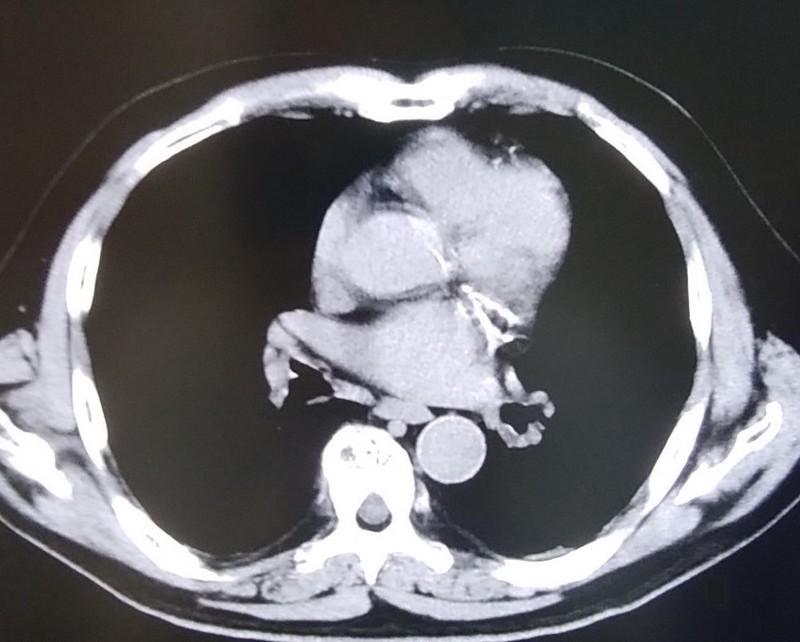

700床を超す著明な国立A病院で肺がんの治療を十分に受けていた建設大工さんの胸部CT写真が写真1です。明らかな胸膜プラークを認めるのですが、その病院の呼吸器内科医も放射線科医も全く認識していませんでした。そんな中、ご家族がアスベスト(石綿)による可能性を疑い、病院の事務でCD-ROMを借用し、セカンド・オピニオンとして、アスベスト関連疾患の専門医がいる「ひらの亀戸ひまわり診療所」に読影依頼をしました。

ひまわり診療所の医師である名取が診療情報提供書で胸膜プラークをご指摘させて頂き、この患者さんは数か月で労災認定されました。肺がんの治療に優れた病院が、石綿やアスベストとの関連を余り知らない典型例の方です。

写真1 国立A病院 胸膜プラーク